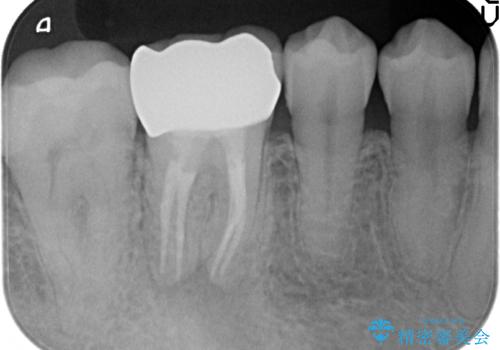

- ものを咬むと右下の奥歯が疼くといらっしゃった方の症例です。

検査の結果X線上で右下6に根尖病変を認めたため、再根管治療を行いました。

症状が治まったのを確認後、オールセラミッククラウンによる補綴を行いました。